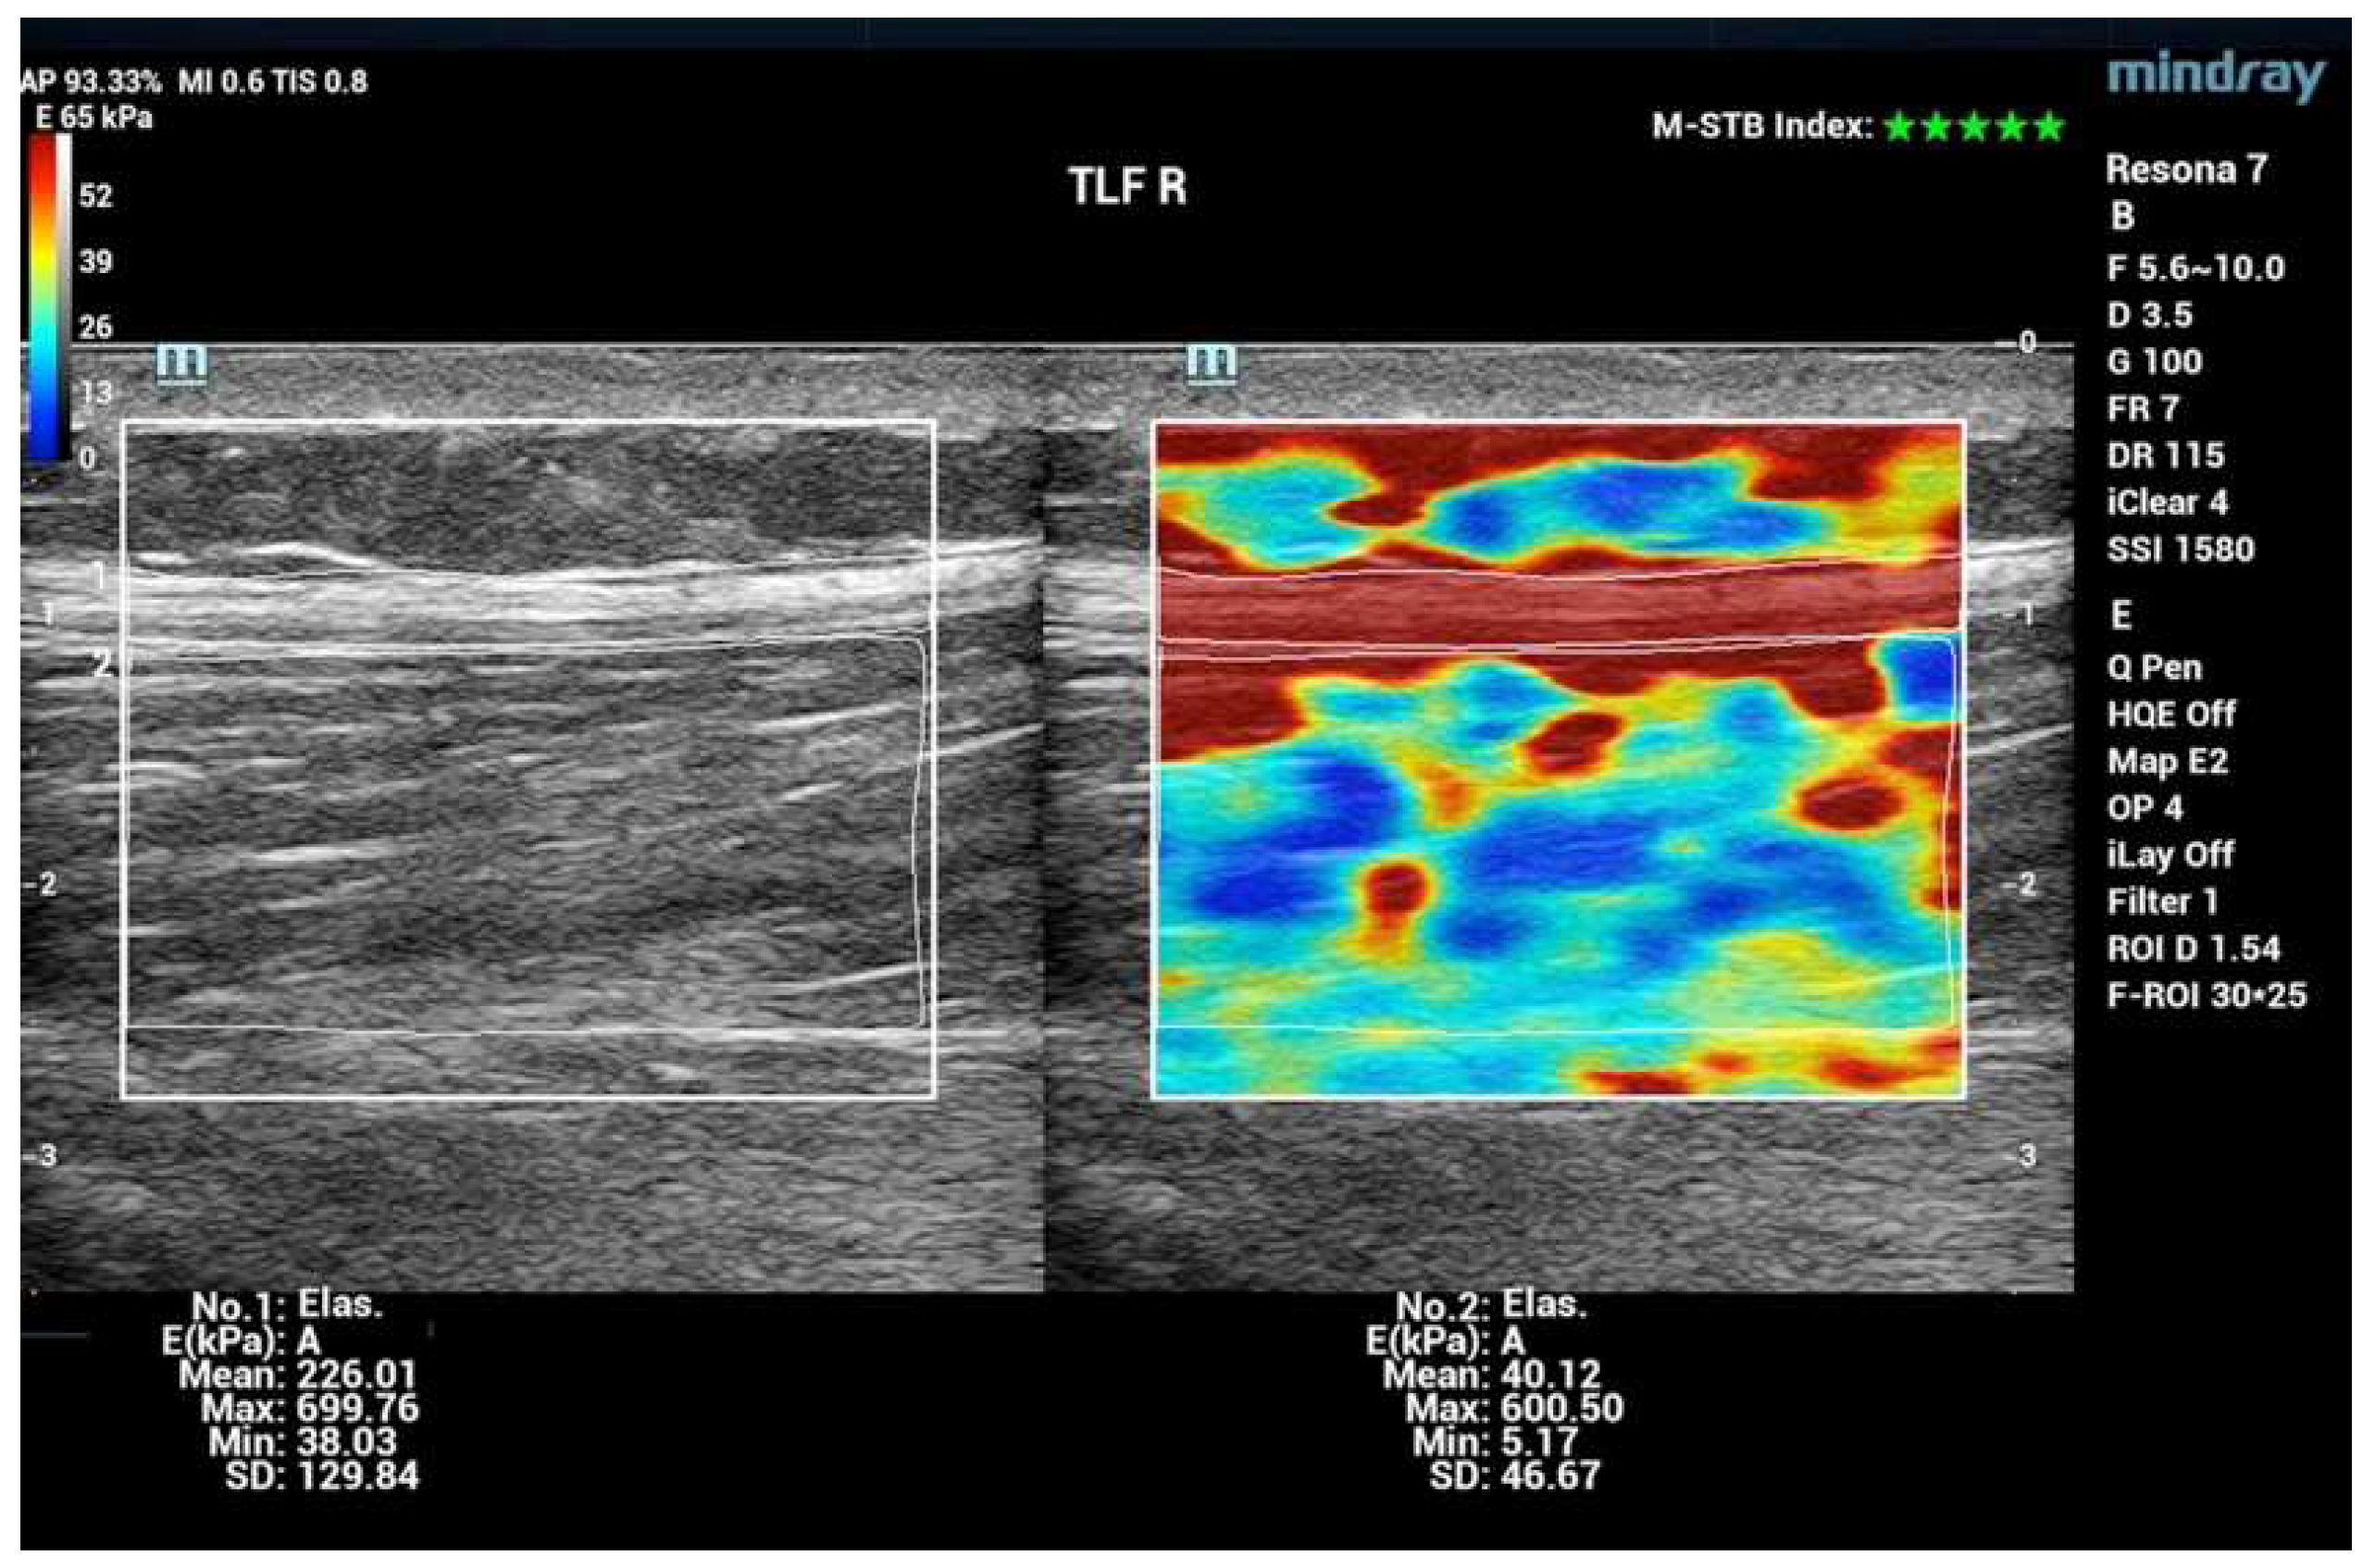

| 5 | Thoracolumbar fascia TLF L4/5 L | Line ilium upper margin 2 cm paravertebral proc. spinous process |

| 6 | Thoracolumbar fascia TLF L4/5 R | Line ilium upper margin 2 cm paravertebral spinous process |